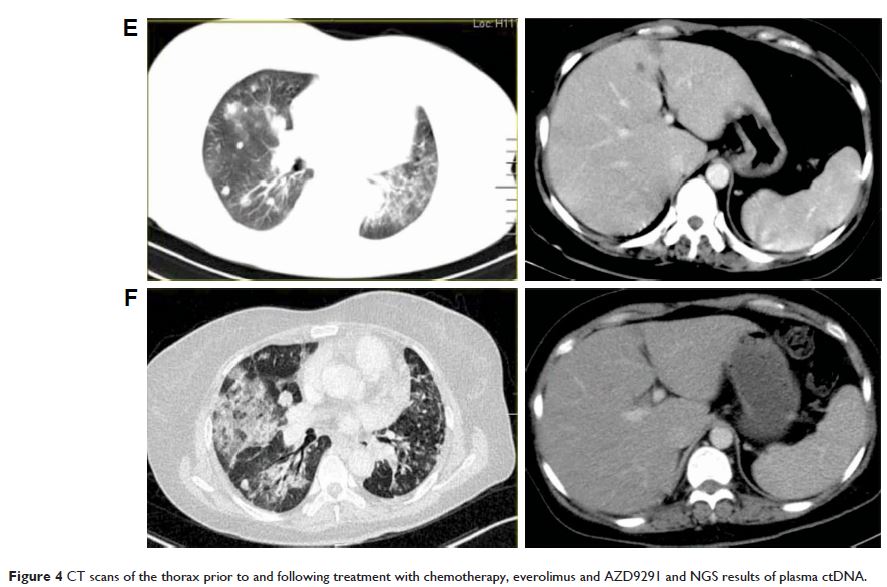

Case Report

- 作者:Li Xu, Qian Z Wang, Lin Wu

- 期刊:OncoTargets and Therapy